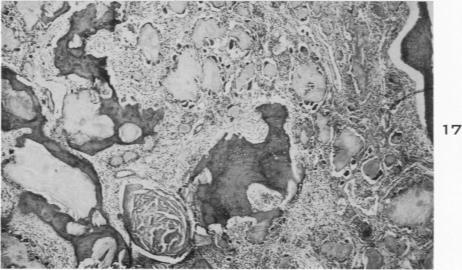

Pathologic changes in gout; survey of eleven necropsied cases.

Am J Pathol. 1956 Sep-Oct;32(5):871-95.